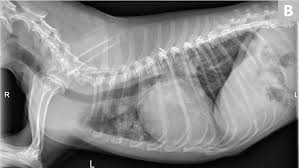

A definitive diagnosis of lung cancer requires a sample of tissue (biopsy). X rays are very helpful in the diagnosis of lung cancer in dogs. Primary lung cancer are frequently located in the caudal (towards the hind end of the pet) lung lobes, however can be located in any lung lobe and are usually a single mass in the lungs, unless the tumor has spread. If your dog has a chronic cough, you'll need to rule these out. The first of these possibilities could be investigated by bronchoscopy. A definitive diagnosis of lung cancer requires a sample of tissue (biopsy). The second kind of lung cancer in dogs is called metastatic lung cancer, which means the cancer originated somewhere else in the body, but has spread to the lung. Bacterial pneumonia is an inflammation of the lung usually caused by bacterial or viral infection but can be caused by inhalation of an irritant. The respiratory system consists of the large and small airways and the lungs. Lung cancer is actually the number one killer when it comes to cancers. But in some rare cases, it may be a lung cancer (primary or secondary). In both cases, you may have. Typical signs of bacterial pneumonia include fever, difficulty breathing, lethargy and coughing.

Primary lung cancer are frequently located in the caudal (towards the hind end of the pet) lung lobes, however can be located in any lung lobe and are usually a single mass in the lungs, unless the tumor has spread. My dog had pneumonia come on quickly this last august, we took her to the local er at 3am when we noticed her breathing labored and strange behavior. A white spot amidst the normal black lungs can therefore be a cancer, infection. Signs of the primary tumors in dogs. I haven't touched cigarettes a day in my life. Lung cancer often misdiagnosed as pneumonia urges requests for second medical opinions. Lung cancer is actually the number one killer when it comes to cancers. A definitive diagnosis of lung cancer requires a sample of tissue (biopsy). His appetite is basically normal though his blood work shows that he is anemic. 3 doctors agree send thanks to the doctor Other common respiratory diseases that might make you worried about cancer are …. Malignant tumors trigger inflammation in surrounding normal lung tissue, and they may obstruct. Pneumonia and lung cancer both affect the lungs but one is easily treatable and the other is potentially life threatening.

Bronchoscopy would also provide the opportunity to biopsy the lung and obtain mucous from the lung for. Other common respiratory diseases that might make you worried about cancer are …. As these can also be caused by other disease, diagnostics include a full physical exam, blood work, radiographs, and may also require bronchoscopy with. If you have lung cancer, it may be more difficult for your doctor to diagnose pneumonia. Lung cancer develops due to the overgrowth of. Lung cancer often misdiagnosed as pneumonia urges requests for second medical opinions. To investigate the mode of clinical onset of pulmonary carcinoma, 232 inpatients with this diagnosis were also stud … The respiratory system consists of the large and small airways and the lungs. A retrospective study of 1011 hospitalized patients with pneumonia was undertaken to assess the value of routine convalescent chest radiography for detection of underlying lung cancer. Pneumonia and lung cancer both affect the lungs but one is easily treatable and the other is potentially life threatening. Your veterinarian may recommend an fna and cytology or a biopsy, to confirm the diagnosis, and determine exactly what kind of lung cancer is present. Persistent chest infections can be signs of something more serious than pneumonia, and unfortunately, it. This is not to say the effects on a loved dog's body are the same as an infection.